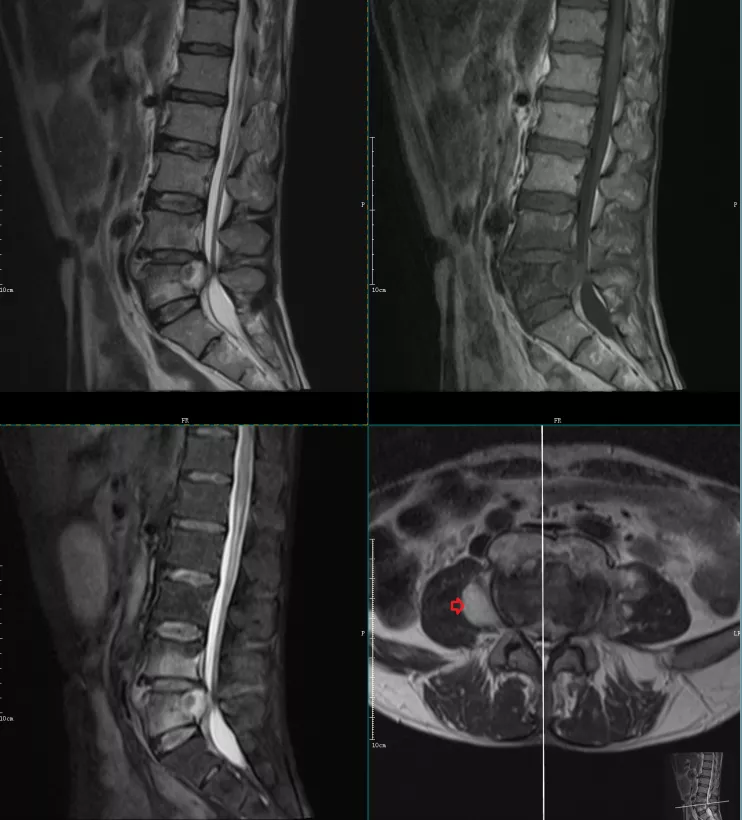

本例患者为l5s1的终板炎及突出的椎间盘钙化